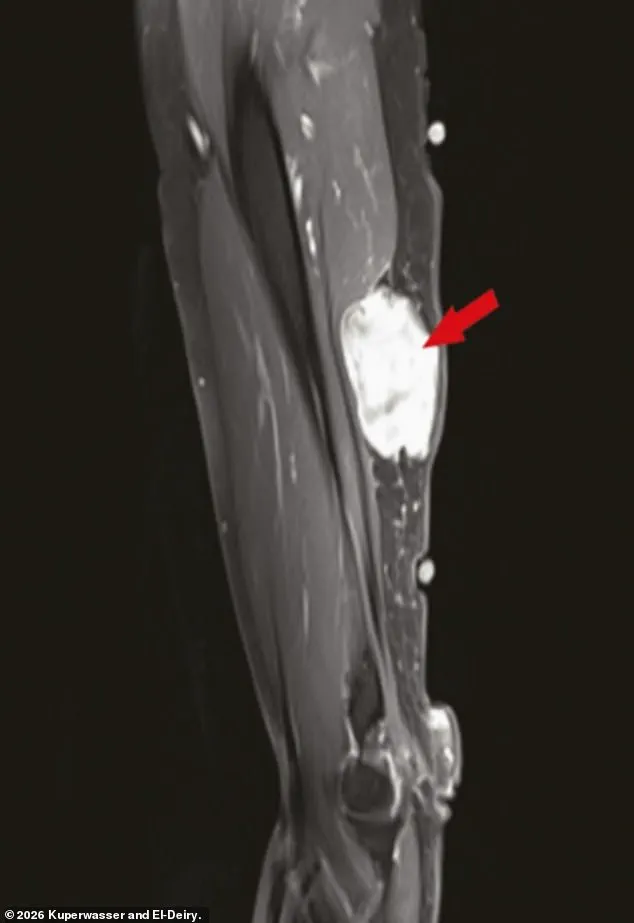

El-Deiry and his co-author, Charlotte Kuperwasser of Tufts University, also highlighted case reports of localized cancer growth near injection sites, which they said warranted further investigation.

The paper documented 333 cases of cancer diagnosed within weeks or months of vaccination or booster shots.

Some of these cases involved sudden flare-ups of slow-growing cancers that had previously been stable, while others suggested that vaccines might have reactivated viruses like human herpesvirus 8, which is linked to certain cancers.